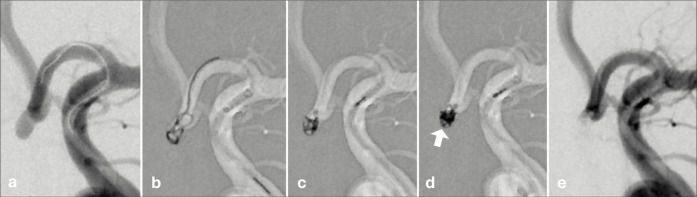

Background: Coil embolization for cerebral aneurysms is an important technique and is not likely to be replaced in the foreseeable future. Recently, the Target Tetra detachable coil (TTDC) has become available, thereby raising expectations for a safer embolization in small aneurysms. Based on our experience, we report the behavioral characteristics and effective utilization of TTDCs.

Methods: We analyzed 28 patients who underwent surgery using the TTDC for intracranial aneurysms between December 2023 and November 2024.

Results: Five cases were treated using the TTDC only. In four of five cases, the aneurysm height was <3 mm. In terms of complications, intraprocedural rupture occurred in two cases and thrombosis in two. None of the patients presented with delayed hemorrhage during the follow-up period.

Conclusion: The TTDC coils cluster at the tip of the microcatheter. Thus, effective embolization can be achieved by filling from the deeper available space. Based on the behavioral characteristics of TTDCs, it is not only beneficial as a finishing coil but also plays a role in filling. We believe that TTDCs may be a useful option for embolizing small aneurysms, including ruptured ones that were previously challenging to treat, and cases in which microcatheter stability are compromised.